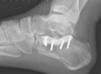

Mala consolidación tipo II: exostosis lateral prominente y artrosis subastragalina (fig. 9). Tratamiento mediante exostectomía lateral, tenólisis de peroneos y artrodesis subastragalina con injerto estructural en bloque (figs. 10 y 11).